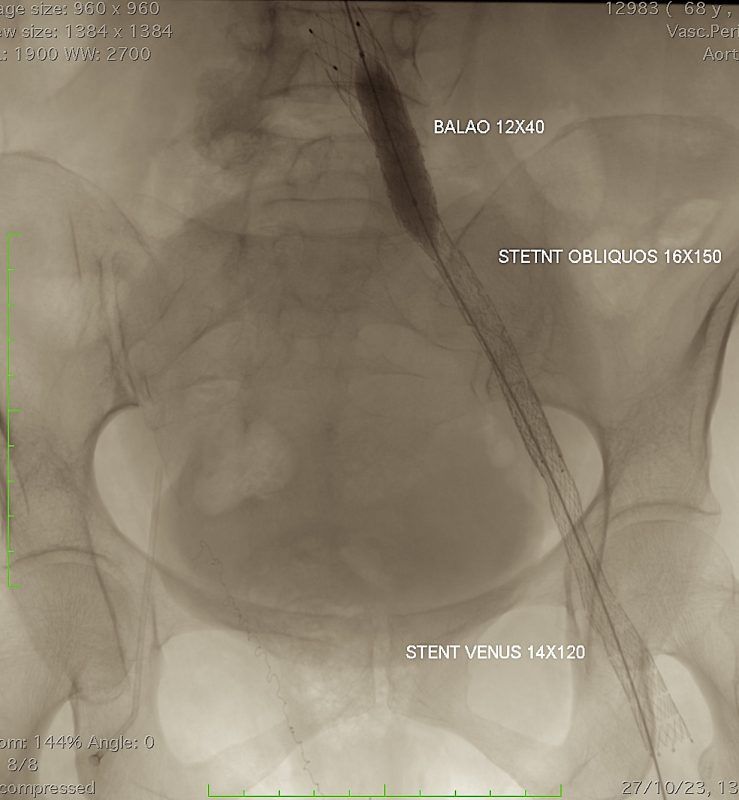

Assista este video onde relato um caso de desobstrução e implante de Stent nas veias ilíacas esquerdas ocluídas há vários anos.